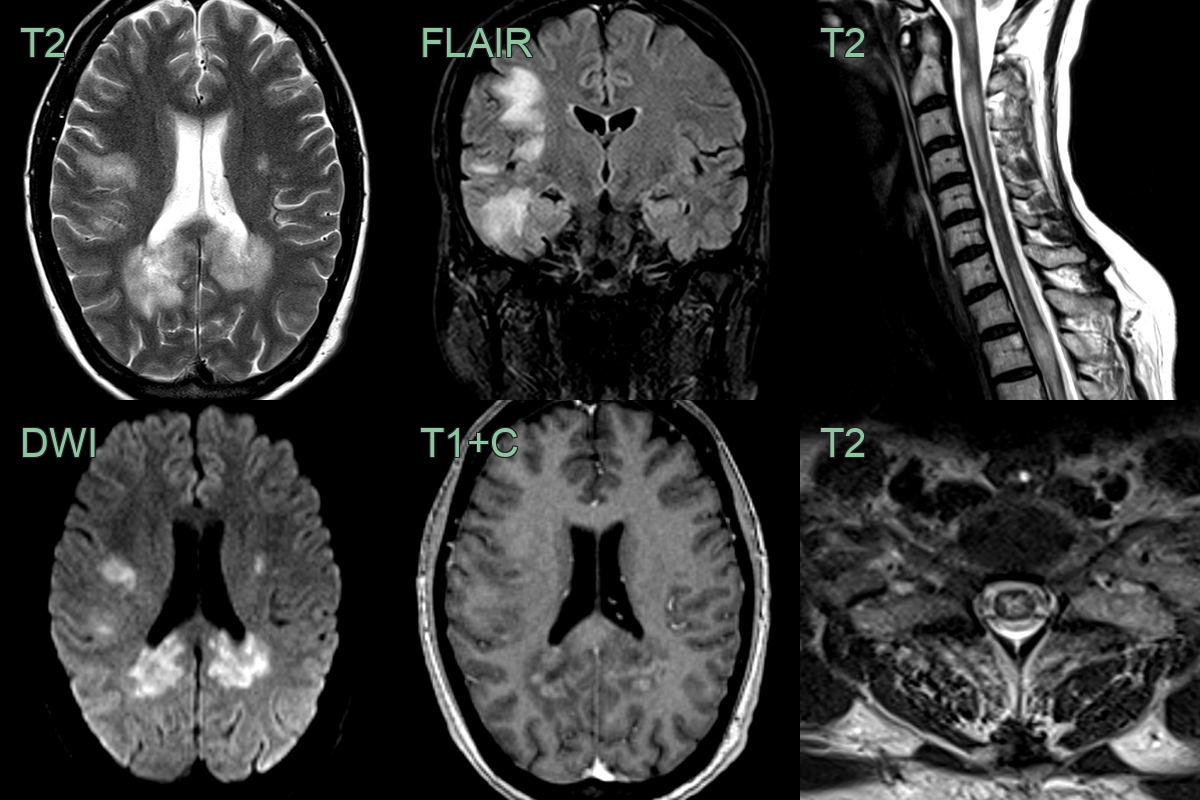

- A 40 year old presented with confusion and upper and lower limb weakness and sensory disturbance.

- MRI showed extensive white matter lesions within both cerebral hemispheres associated with diffusion restriction and peripheral enhancement.

- In the cord, there were multiple swollen mainly central short segment cord lesions.